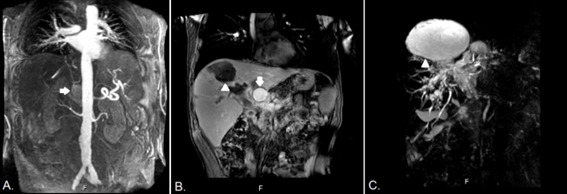

A 69-year-old man underwent liver transplantation with a deceased donor for cirrhosis secondary to steatohepatitis. The arterial anastomosis was performed between the celiac trunk of the donor and the hepatic artery of the recipient. In the second postoperative month, he developed abdominal pain and abnormal liver function tests. MRI angiography and subsequent digital angiography confirmed a 50 x 60 mm hepatic artery pseudoaneurysm (PAH) with dilation of the bile duct and bilomas in both hepatic lobes. Endovascular treatment could not be performed due to the absence of contrast passage to the intrahepatic branches during angiography. A surgical ligation and resection of the PAH that compromised both hepatic arteries was chosen. The primary anastomosis was not viable because it was not possible to identify a viable proximal end or ostium. Given the ischemic compromise of the bile duct, an exception route for re-transplantation was requested from INCUCAI, thus entering the waiting list and accessing a new graft 30 days later. His subsequent evolution was favorable. Now he's asymptomatic under follow-up after 9 years of the liver re-transplantation.